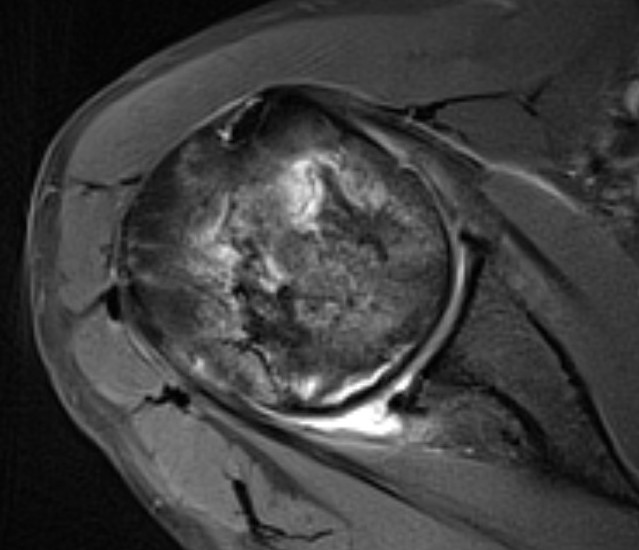

Pathology

Superior head collapse at 90° mark

- area of peak contact stress in abduction

- glenoid rarely affected

- soft tissue and subscapularis rarely contracted

MRI

Sensitivity and specificity approach 100%

T1

- areas low signal intensity on T1 representing edema

- areas of high signal intensity thought to represent blood flow

T2

"Double line sign"

- highly specific for AVN

- inner bright line representing granulation tissue

- outer dark line representing sclerotic bone